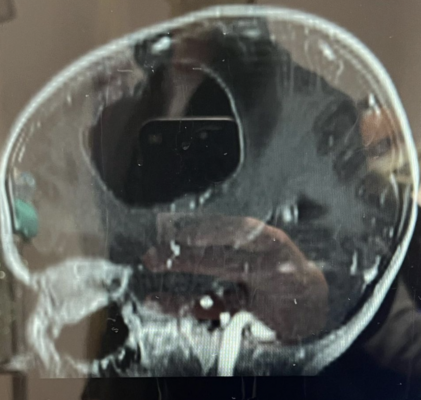

Теперь в семье Смита случилось новое несчастье — младший ребенок и единственная дочь Смита Слоун была вынуждена перенести срочную операцию по удалению крупной раковой опухоли мозга.

Слоун перенесла 10-часовую краниотомию, врачам удалось полностью удалить опухоль.

Ее отец показал в соцсетях, как выглядела опухоль перед процедурой.

В соцсетях Смит рассказал, что у Слоун обнаружили редкую опухоль, по которой врачи не могут с уверенностью дать прогноз по восстановлению девочки.